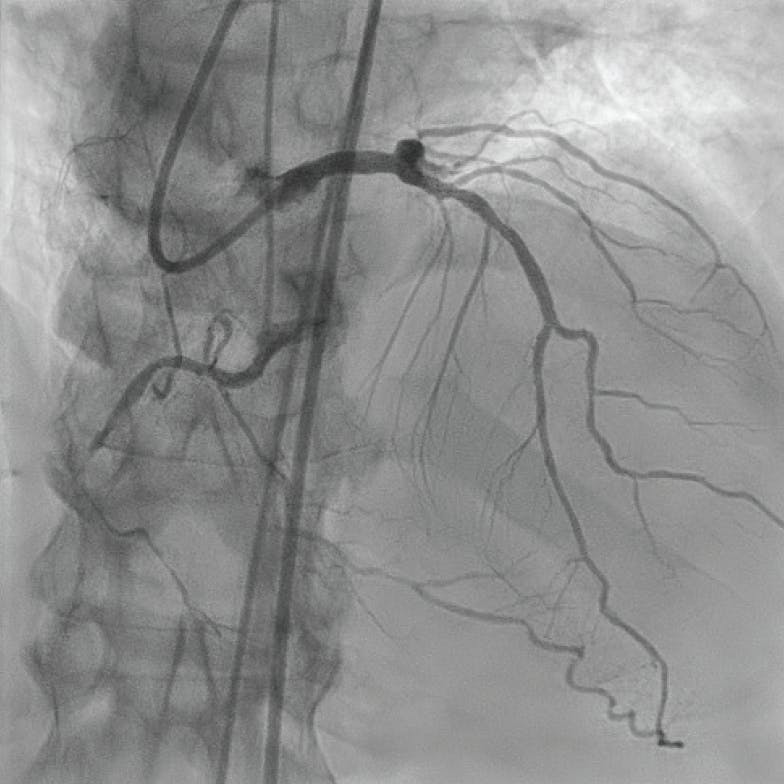

An XB 3.5 guide catheter was utilized to access the left coronary system, and the circumflex lesion was crossed with a Hi-Torque Pilot 50 guidewire (Abbott) utilizing back support with a Corsair microcatheter (Asahi Intecc USA, Inc.), and distal intraluminal position was confirmed with contrast injection thru the Corsair microcatheter (Figure 3). The occlusion of the circumflex was crossed and the distal wire was positioned in the obtuse marginal (OM) branch with utilization of the Speed-Torque®, a novel torque device. Angioplasty of the OM1 was completed with a 2.0- X 20-mm balloon, and a 2.5- X 32-mm Synergy stent (Boston Scientific Corporation) was subsequently placed. A Runthrough wire (Terumo Interventional Systems) was introduced to the circumflex continuation at a 60° angulation with the assistance of the Speed-Torque® device. A 3.5- X 24-mm Synergy stent was then placed at the circumflex with overlap to the OM1 stent, postdilation was completed with a 4.0-mm noncompliant balloon, and intravascular ultrasound (IVUS) confirmed good stent-to-wall apposition (Figure 4).

Figure 3. Distal OM angiography confirming the intraluminal position.

Figure 4. Completed circumflex and OM intervention.